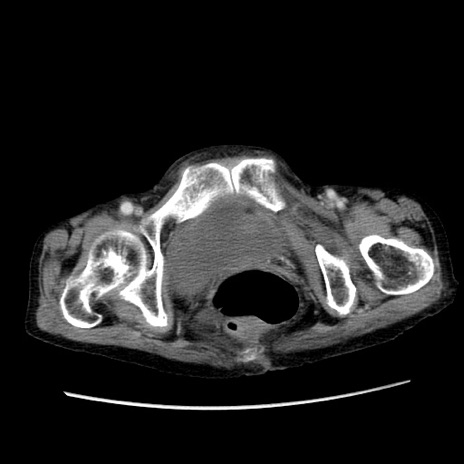

症例25(横断像)

【症例】80歳代女性

【主訴】胸のつかえ感

【現病歴】約9時間前に食後から胸のつかえた感じあり、嘔吐あり、来院。

【既往歴】胃癌(全摘)、胆摘、虫垂炎

【身体所見】心窩部に圧痛あり、反跳痛なし。

【データ】WBC 5700、CRP 0.05